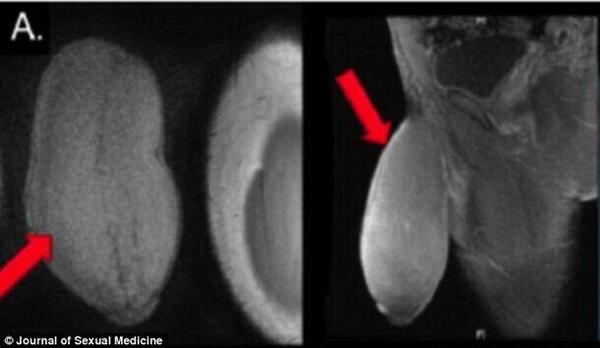

【环球网综合报道】据“俄罗斯世界”新闻网2月13日消息,美国一名17岁的少年接受阴茎缩小手术,为世界首例。

据报道,这名17岁少年的生殖器官长度为18厘米,而周长为25厘米,据医生介绍,这种情况是不正常的,可能引起阴茎的不正常勃起,即不受控制的长时间勃起。而这名少年也表示,这些身体上的异常使他不能进行某些正常的体育锻炼以及拥有性生活。

阴茎缩小手术进行的十分成功,手术后该少年表示心情十分喜悦以及激动。(实习编译:吕菁 审稿:翟潞曼)